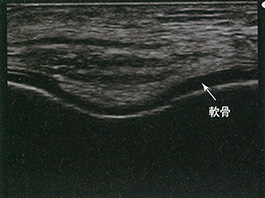

軟骨下骨の高輝度線状エコーとそれを覆う軟骨の均質な無エコー像が描出される。この部分は荷重部ではない。 |